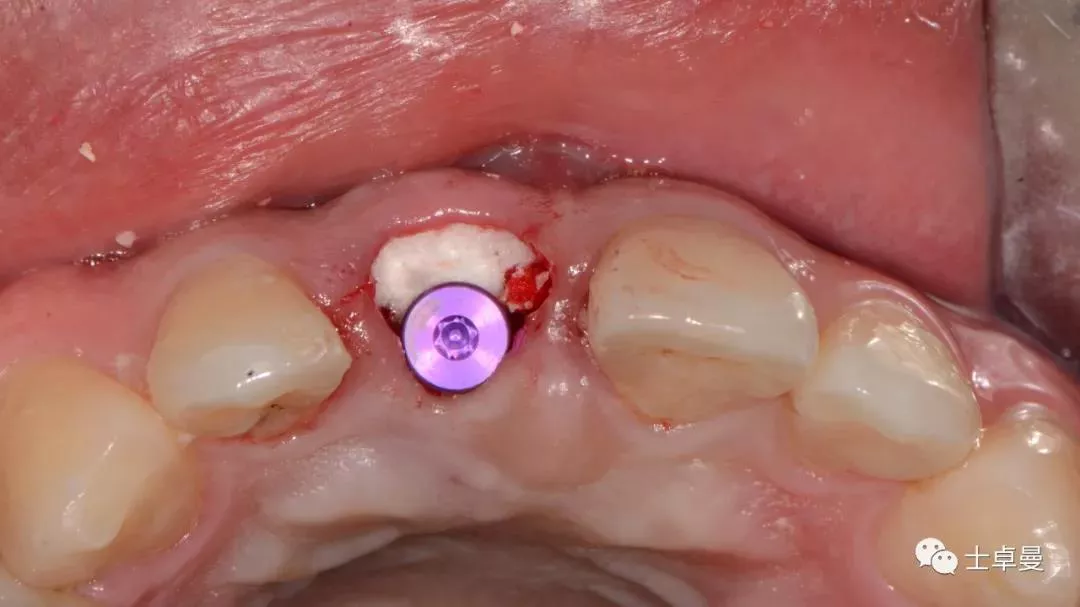

· 唇侧植入骨粉0.25g,胶原骨100mg;

· 用临时基台制作个性化愈合帽;

种植体植入后,植体唇侧间隙内填塞骨粉0.25g,胶原骨100mg,安放愈合帽,明胶海绵暂时封闭创面